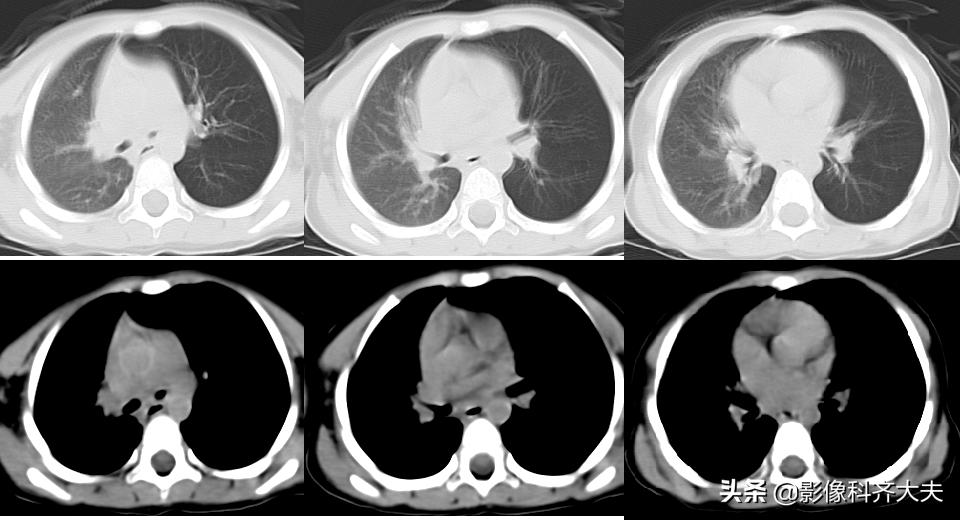

病例1、病史:患儿,女,一岁半,咳喘两周,病前有“开心果”吸入史。

图为轴位及冠状位重建图显示异物:红色箭头为异物的位置,冠状位显示尤为清晰。